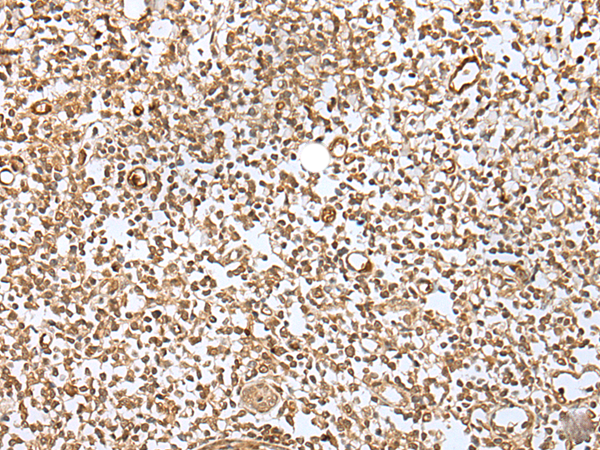

IHC positive control: |

Human tonsil and human breast cancer |

IHC Recommend dilution: |

30-150 |